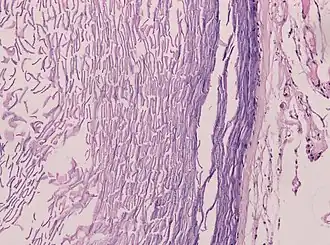

Epidermoid cysts are usually diagnosed when a person notices a bump on their skin and seeks medical attention. The definitive diagnosis is made after excision by a pathologist based on microscopic appearance of a cystic lesion lined by cornified epithelium containing lamellated keratin without calcifications. They can also be seen as isointense lesions on MRI or hyperintensities on FLAIR.

Histopathology, showing a keratinizing stratified squamous epithelium, and a lumen containing keratin flakes -

Histopathology showing epithelium and lamellated keratin (left)